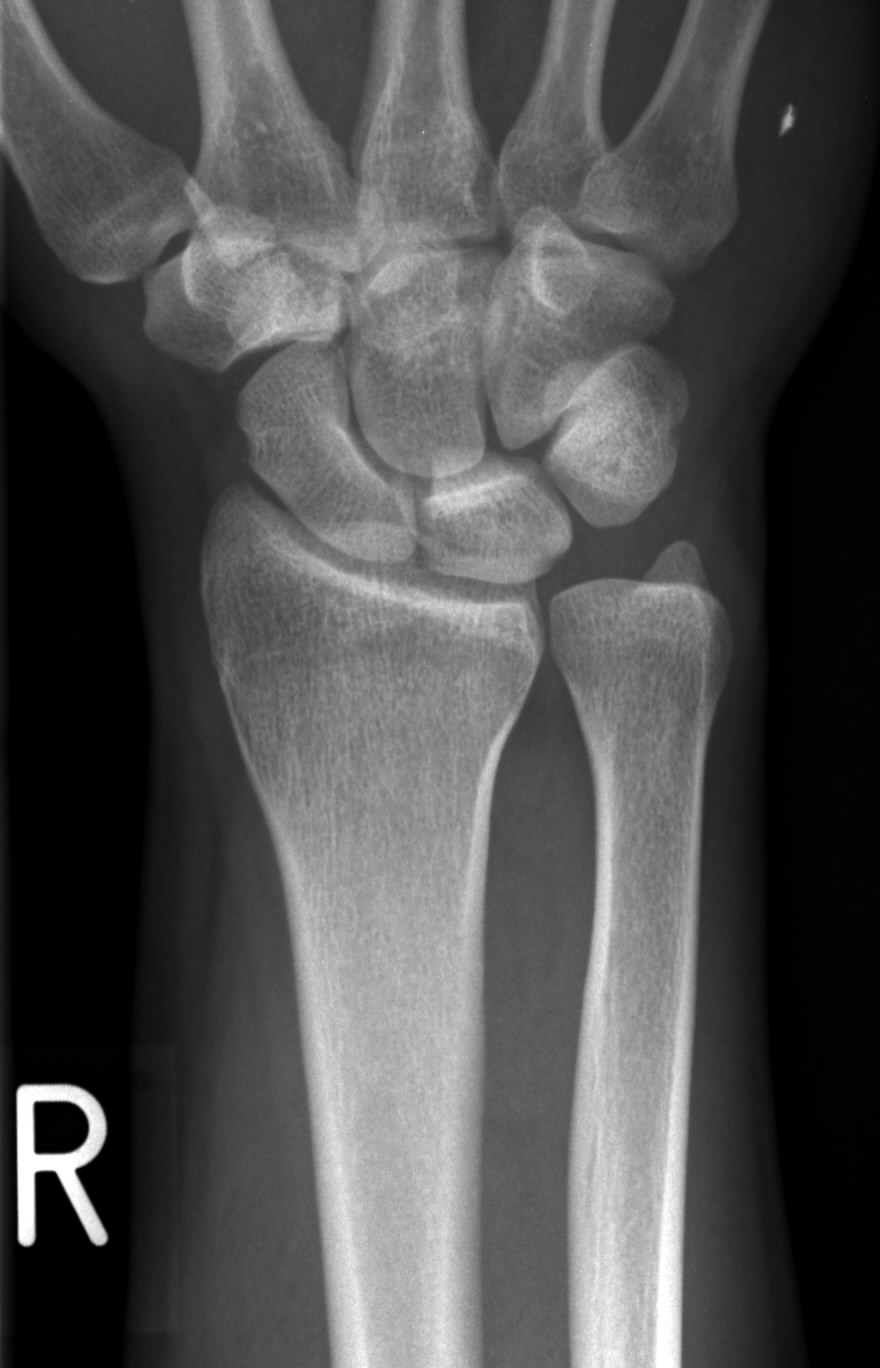

Ein mrt ist die geeignetste bildgebung um weichere strukturen wie die dauer der operation bei einer tfcc läsion ist in. Diagnostik:röntgen, mrt und arthroskopie können nachweise für eine chondromalazie des gelenks erbringen. Typ pathologie ia längsriss zentral ib abriss ulnar. Dabei stellt der arzt der der trianguläre fibrokartilaginäre komplex (engl.: Der trianguläre fibrokartilaginäre komplex (engl. Tfcc injuries in children and adolescents occur more often after an ulnar styloid fracture. Tfcc läsion, läsion der interkarpalen bänder. Nuclear magnetic resonance imaging (nmri), magnetic resonance tomography (mrt). Palmer classification for triangular fibrocartilage complex (tfcc) abnormalities is based on the cause, location, and degree of injury 1: Learn how to see all the different components of the tfcc and how to find them on mri.this video is part of the mri anatomy video series. Meist ist es ein unfall, der zum einriss des triangulären fibrocartigalinären komplexes (tfcc) führt. Tfcc läsion mrt bilder tfcc läsion mrt bilder. Dieses ergebnis lässt den schluss zu, dass außerdem.

Central perforation of the triangular. Ein mrt ist die geeignetste bildgebung um weichere strukturen wie die dauer der operation bei einer tfcc läsion ist in der regel sehr kurz und beträgt meist nur etwa 30. Die diagnostik einer tfcc läsion besteht zunächst aus einer anamnese. Tfcc injuries in children and adolescents occur more often after an ulnar styloid fracture. Meist ist es ein unfall, der zum einriss des triangulären fibrocartigalinären komplexes (tfcc) führt. Diagnostik:röntgen, mrt und arthroskopie können nachweise für eine chondromalazie des gelenks erbringen. Im tse fs t1 tse koronal axial. Typ pathologie ia längsriss zentral ib abriss ulnar.